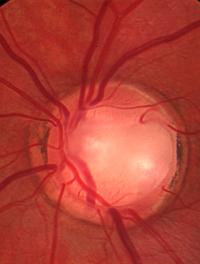

Les premiers résultats publiés de la United Kingdom Glaucoma Treatment Study (UKGTS) montrent, pour la première fois dans un essai [...]